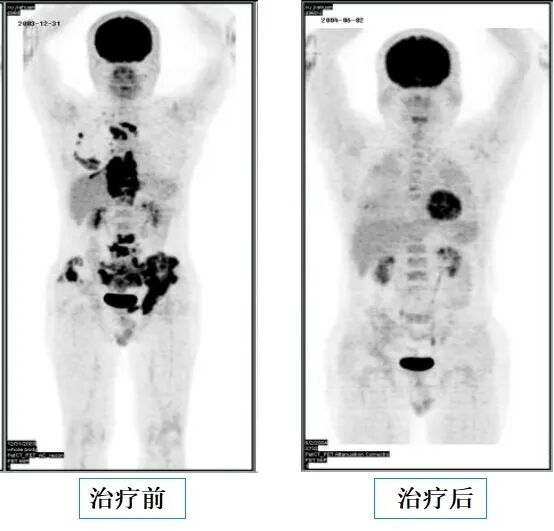

淋巴瘤化疗前后对比